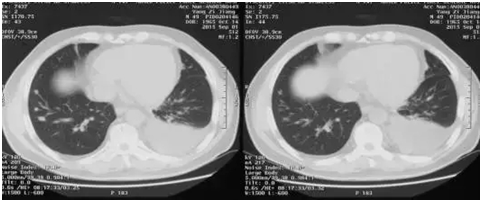

赵先生的情况与杨先生很相似,他在2014年6月发现肝脏肿瘤,并进行手术切除,当时肿瘤大小也不超过3公分,属于小肝癌。但是半年以后,赵先生就出现肺部转移,他进行过放疗、射频等局部治疗,也服用过多吉美,但是肝功能恶化,腹泻严重,无法继续服用,期间甲胎蛋白从251上升到2890。在医生的建议下,他也进行了PD-1抑制剂的注射,4个周期PD-1治疗以后,肺部病灶明显缩小(见 图3),甲胎蛋白也降至正常范围。赵先生高兴的对医生说,疗效好的他都不敢相信,PD-1抑制剂给了他第二次生命。

图3 PD-1治疗后,红色标示肿瘤